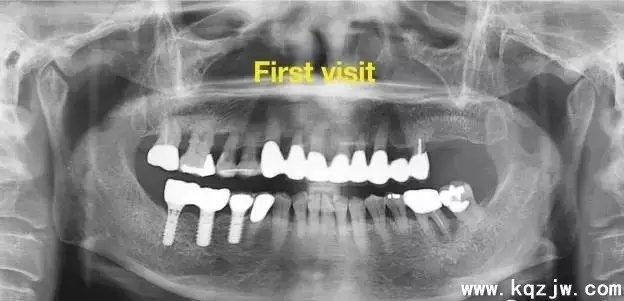

兒童牙外傷是口腔正畸兒童牙科門診的常見病,常發(fā)于上頜前部,而牙齒完全性脫位又是兒童牙外傷中較為嚴(yán)重的一種。我科自1999.9-2004.6共收治16例7-13歲21顆脫位牙,對(duì)其進(jìn)行固定正畸技術(shù)即刻再植,術(shù)后定期隨訪1-4年,患牙保持率100%。

本科共收治病例16例,男性15例,女性1例,均為外傷完全性脫位。16例病例中均不含頜骨骨折并輕度牙槽突骨折,其中磕傷13例,他人擊傷3例。21顆外傷脫位牙全部為恒上切牙,其中單牙11例,雙顆牙(連續(xù))6例。

脫位的21顆牙中:19顆無痛、無變色、無松動(dòng)、根尖陰影牙周膜間隙無增大。

2顆有輕度叩痛,根尖有陰影、有輕度變色(后經(jīng)根尖誘導(dǎo)形成術(shù))、叩痛消失、根尖陰影消失,總的患牙保持率100%。